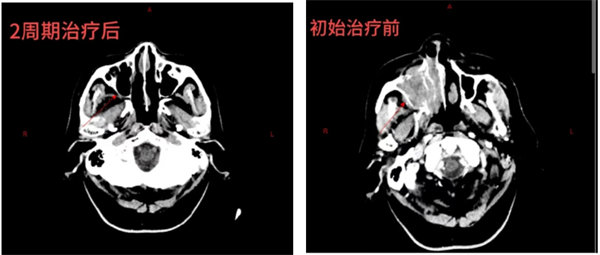

當得知院內有一種靶向治療藥物短缺后,副院長湯淑斌立即安排藥劑科走綠色通道快速進藥,本著以患者為中心,一切為了病人,急病人之所急的理念,讓病人得到了最快的治療。經過2周期的治療后,患者眼眶疼痛,面部腫脹疼痛、鼻塞、氣短等癥狀完全消失,目前呼吸順暢,食納精神好。復查CT提示:右側上頜竇腫瘤基本消失。隨著治療的不斷推進,老人的身體狀況不斷好轉,生活質量得到了顯著提升。如今,他不僅能夠重新享受與家人團聚的溫馨時光,還可以進行日常活動。付大爺高興地說:“治療效果太好啦!我沒病啦!太感謝人民醫院血液腫瘤科啦”!